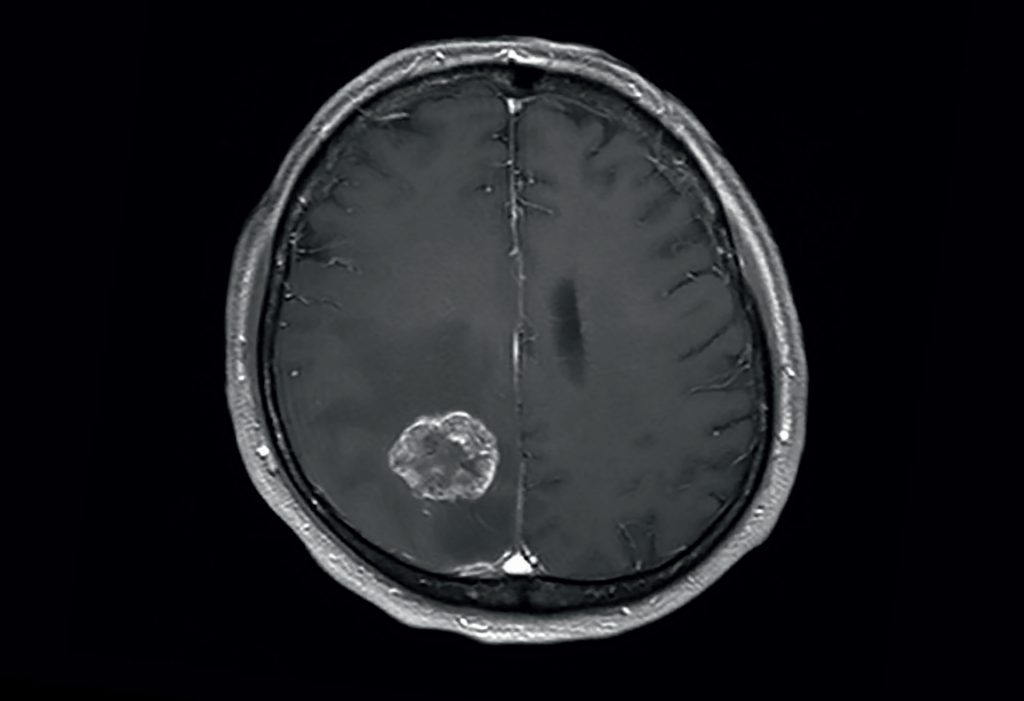

Kernstück der Diagnostik sind bildgebende Verfahren, wobei die Kernspintomographie (MRT) der Computertomographie (CT) überlegen ist.

Die Computertomographie spielt als schnell durchführbares und breit verfügbares Verfahren vor allem eine Rolle in der Notfallmedizin. Größere Metastasen grenzen sich als hypodense oder selten (Malignes Melanom, Chorionkarzinom) hyperdense Struktur gegen das normale Hirnparenchym ab. Da Metastasen aber auch isodens sein können, ist womöglich nur die raumfordernde Wirkung als Massenverschiebung oder die hypodense Formation des Perifokalödems abgrenzbar. Zentrale Einblutungen, wie sie insbesondere bei Metastasen von malignen Melanomen oder Nierenzellkarzinomen vorkommen, sind in der CT gut nachweisbar. In Abhängigkeit von der gewählten Schichtdicke liegt die Nachweisgrenze bei etwa einem Zentimeter, so dass kleinere Metastasen der nativen Computertomographie entgehen können.

Da die Computertomographie einen relativ geringen Weichteilkontrast aufweist, ist die Gabe von Kontrastmittel entscheidend: aufgrund der Störung der Blut-Hirn-Schranke im Bereich der Metastase kommt es zur Anreicherung von Kontrastmittel (Enhancement), das bei Vorliegen einer zentralen Nekrose häufig ring- oder girlandenförmig erscheint.

Kernspintomographie

Die Kernspintomographie weist bei besserer Weichteildifferenzierung, insbesondere nach Gabe von Gadolinium als Kontrastmittel, eine deutlich höhere Sensitivität auf und ist somit geeigneter für die Suche nach Hirnmetastasen. So ist im Vergleich zur CT-Untersuchung die Rate der Patienten mit im MRT nachgewiesenen Hirnmetastasen mehr als doppelt so hoch. Das gilt besonders für sehr kleine Befunde und Metastasen im Bereich der hinteren Schädelgrube. Die Kernspintomographie kann zur Abgrenzung gegen Hirnabszesse oder andere möglicherweise ähnlich imponierende Läsionen um eine Kernspinresonanzspektroskopie ergänzt werden.